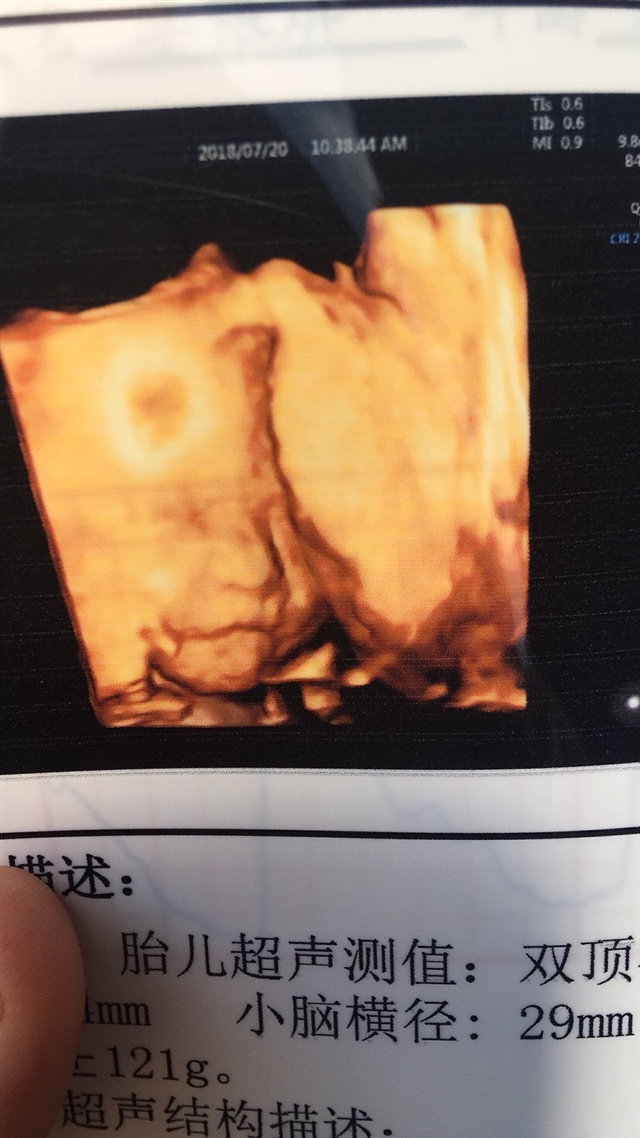

孕29周+4天

应该是女孩